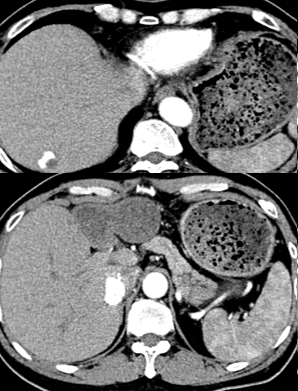

复查CT:

开始改用口服索拉非尼(多吉美)400mg/bid

CT:

AFP:24.4 ug/L

CA19-9: 59.6 U/ml

口服靶向药22个月后复查CT(2017.10.20)

AFP:10989.6 ug/L

CA19-9:60.5 U/ml